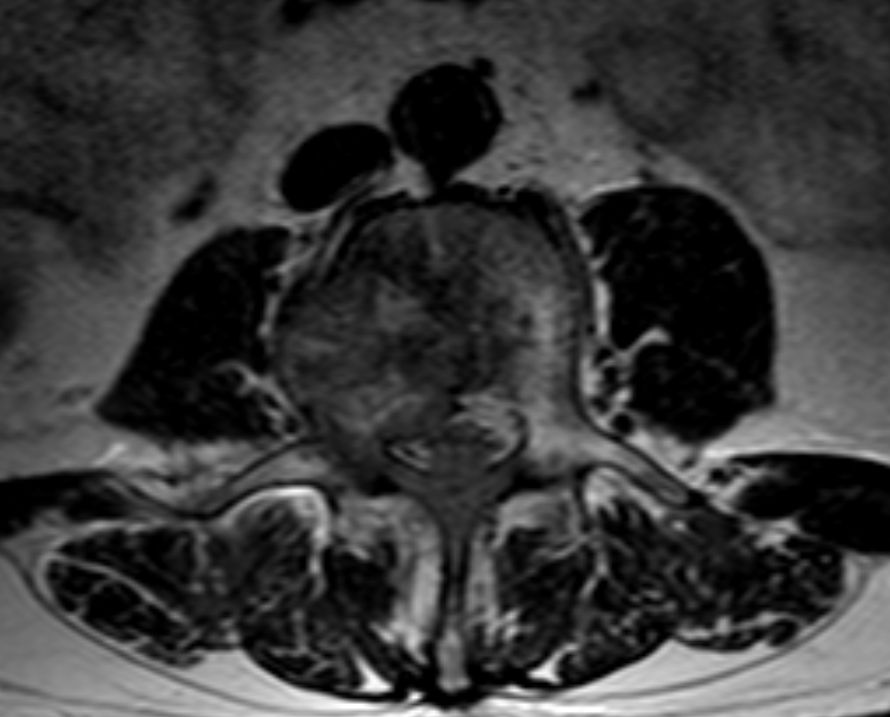

| 14% regionale Lymphknoten, 31% Lunge, 15% Knochen | MRT: Knochenmetastasen

![]() | ||